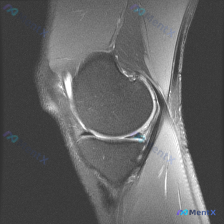

看到一个很有代表性的读片病例,怀疑半月板异常但单张T1加权MRI没有发现明确问题,整理了分析思路和大家分享。 病例核心信息 问题:临床怀疑半月板异常,提供单张膝关节矢状位T1加权MRI,需要做影像观察和分析 影像系统性观察结果 1. 骨性结构:股骨远端、胫骨近端、髌骨轮廓规整,骨髓信号正常,未见骨质...

今天看到一份很有代表性的读片病例,整理出来和大家分享一下,核心问题就是:临床怀疑半月板异常,但是只给了一张膝关节矢状位T1加权MRI,阅片没发现明确异常,这个情况该怎么分析? 先整理一下这份影像资料的基本信息 这是单张膝关节正中矢状位T1加权像,图像质量清晰,没有运动伪影,能看到股骨远端、胫骨近端、...

最近碰到一个有意思的读片病例,患者临床提示半月板异常,但提供的单张MRI并没有看到明确问题,整理一下完整的分析思路给大家参考。 一、病例核心信息 这是一份膝关节矢状位MRI扫描图像,临床问题是排查"半月板异常",我们先对影像做系统性评估: 1. 影像基本信息:这是T2/质子密度加权矢状位图像,清晰显...